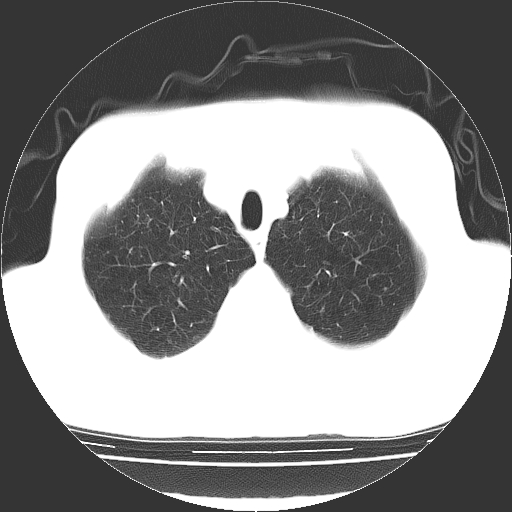

以下是引用hhcckk在2009-1-1 15:38:00的发言:[br]左下肺少许絮状模糊影--考虑感染[br]两肺散在小点状密度增高影--结合病史考虑矽肺?[br]气管壁钙化--可能由于老年退变性引起的